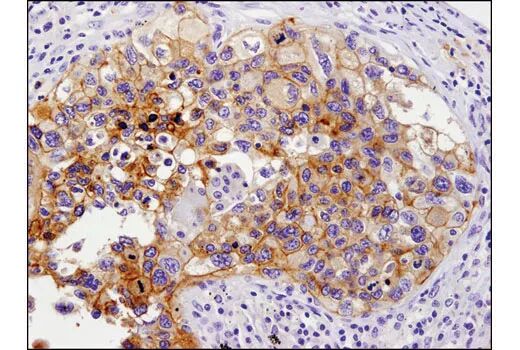

肿瘤生物标志物的检测经常使用 IHC 检测。因为 IHC 让肿瘤和周围的肿瘤微环境的背景可视化,所以它的独特性在于揭示癌症发生和进展。通过 IHC 准确检测需要高度特异性、经过严格验证的抗体试剂。CST提供经过IHC验证的肿瘤免疫研究抗体,帮助研究人员探索肿瘤微环境。

经过IHC验证的肿瘤免疫研究抗体

• 超严格的抗体验证,使用多种分析方法验证

高特异性、高灵敏度、可重复性